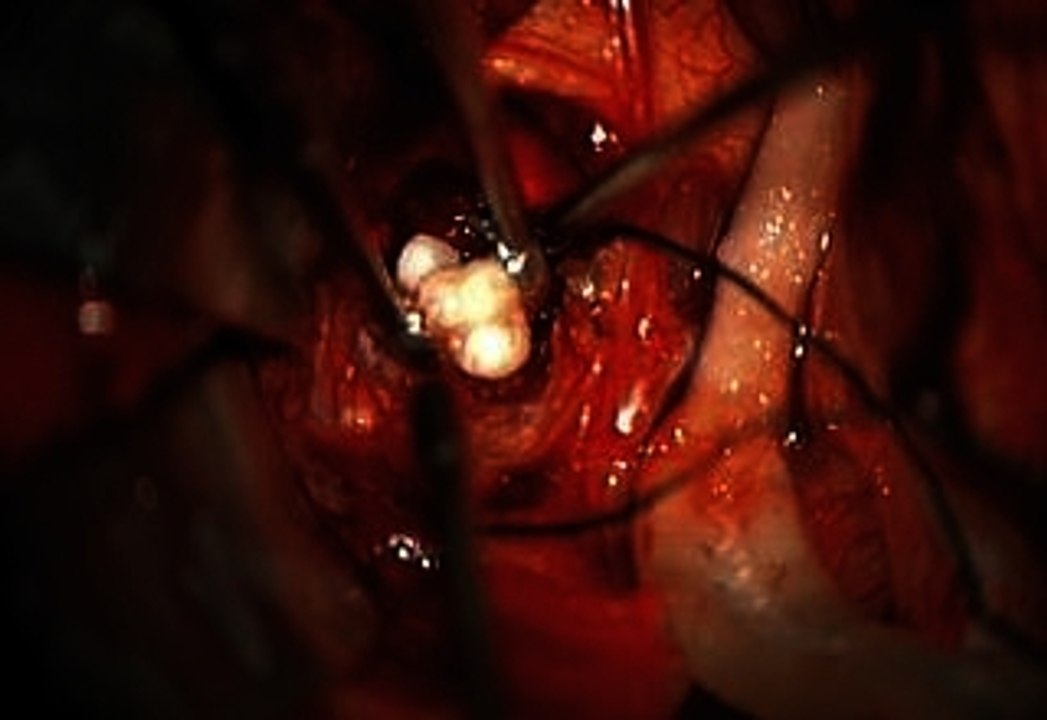

Doctors Remove Tumor In Baby's Brain And Find Teeth 1:24

Doctors Remove Tumor In Baby's Brain And Find Teeth